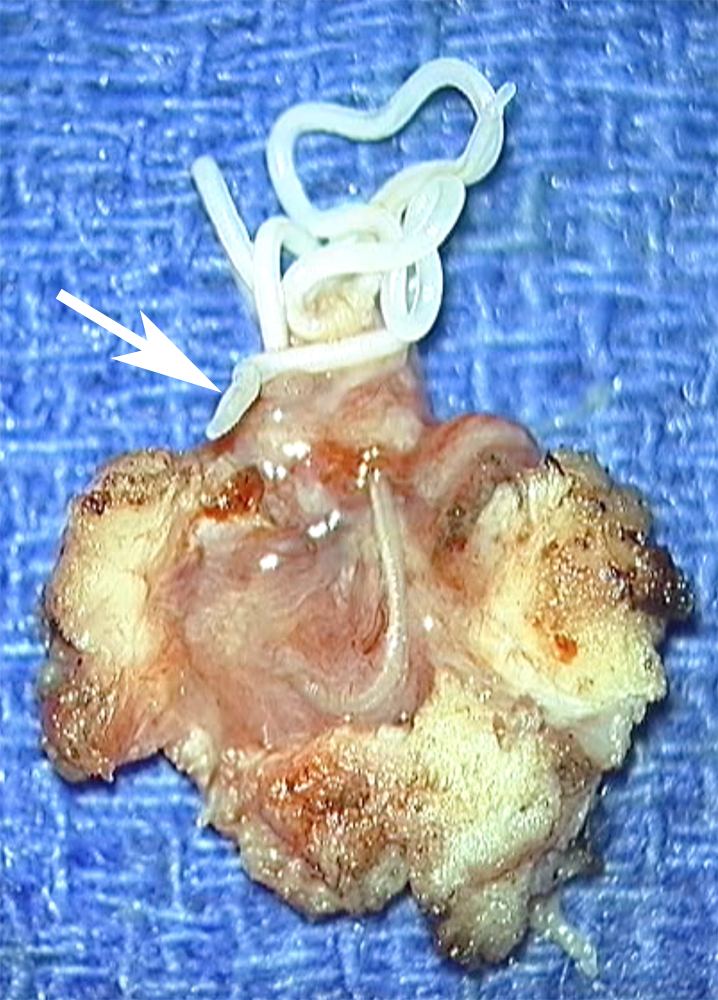

| Figure 5. Vue de la pièce d’exérèse chirurgicale. De la masse tissulaire, on voit sortir, à travers une brèche, une structure filiforme blanchâtre dont des portions sont mobiles (flèches en a, b et c et têtes de flèches en c et d). Notez de fines crêtes visibles en c (flèche). |

L’exérèse chirurgicale du nodule a visualisé lors de son ouverture la présence d’un long ver d’aspect blanchâtre (figure 5), mobile spontanément, long de 12 cm, correspondant aux descriptions de Dirofilaria repens. L’évolution ultérieure a été très favorable.

L’identification de l’espèce repose sur l’analyse du diamètre, de la musculature périphérique et de la cuticule. La filaire Dirofilaria repens est la plus grosse de l’espèce (220-660 microns, avec un diamètre plus grand pour la femelle). Sa longueur est de l’ordre de 10 cm7,11,14. La cuticule

a une surface ornée de crêtes transversales et longitudinales (figure 5c), ce qui donne un aspect festonné sur des coupes transversales, à l’inverse de la surface totalement lisse de la Dirofilaria immitis1. En-dessous se trouvent une couche musculaire, un tube digestif etdeux tubes génitaux. Si la filaire est morte, l’identification devient difficile3,5.